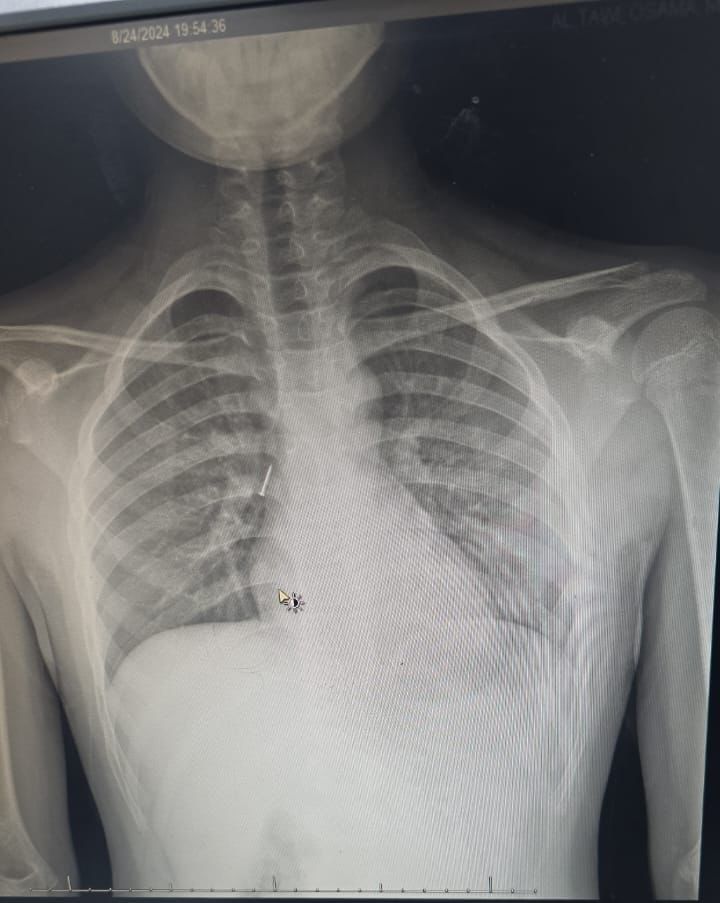

تمكن فريق طبي من قسم جراحة الأنف والأذن والحنجرة في  مستشفى الملك خالد  التابع لتجمع  تبوك  الصحي  بمنطقة  تبوك  من انقاذ حياة طفل في العاشرة من عمره ابتلع مسماراً معدنياً مما تسبب له في ضيق في التنفس في الجهة اليمنى من الرئة وتضييق في الصدر.

وقال الفريق الطبي المعالج بأن الطفل وصل للطوارئ وكان يعاني من آلام شديدة في الحلق وضيق في التنفس وتم وضعه على الأكسجين بعد أن تم قياس العلامات الحيوية له , وبعد تقييم الحالة من قبل أخصائي الطوارئ وأخصائي الأطفال وأخصائي الأنف والأذن والحنجرة تقرر نقل الطفل إلى العناية المركزة للأطفال كما تم عمل أشعة مقطعية دقيقة على الشعب الهوائية حددت مكان المسمار المعدني بدقة.

وأكد الفريق الطبي المعالج بأنه تقرر على الفور إجراء عملية عاجلة لاستخراج المسمار المعدني بمنظار الشعب الهوائية تحت تخدير كامل للطفل من قبل فريق جراحة الأنف والأذن والحنجرة والتي تكللت ولله الحمد بالنجاح ولقد استغرق إجراء العملية ساعة كاملة, بعدها خرج الطفل من المستشفى وهو يتمتع بصحة جيدة ,مع المتابعة في عيادة الأنف والأذن والحنجرة.